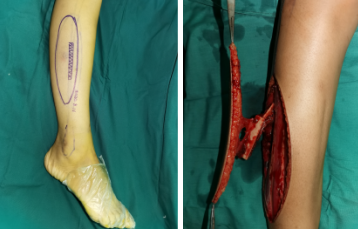

皮瓣术前照片

术中

术后DR

术中,根据创面缺损的大小、形状设计皮瓣并划线标记,医生游离血管蒂长度满足受区要求、血供良好的皮瓣,移植到脚部的残损创面,在显微镜下细致吻合血管、神经。皮瓣供区则直接拉拢缝合,将来不会影响腿部的使用功能。